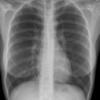

paraspinal lines

Date: 10/23/2010

Views: 3546

Views: 3261

Views: 3130